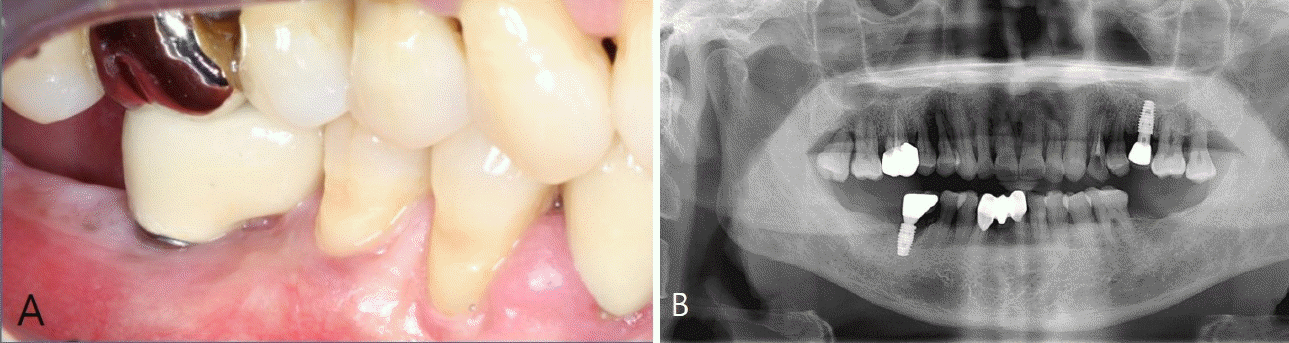

Figure 2.

A. Clinical photograph before treatment. B. Clinical photograph of the #33 implant site. C. Quantitative light-induced fluorescence (QLF) image of #33 shows plaque accumulation on the implant surface. D. Periapical radiograph reveals advanced bone loss around #33. E. Clinical photograph of the #43 implant site. F. QLF image of #43 shows plaque accumulation on the implant surface. G. Periapical radiograph reveals bone loss around #43. Plaque accumulation is clearly visualized in the QLF images (white arrow), including biofilm not detectable by visual inspection.